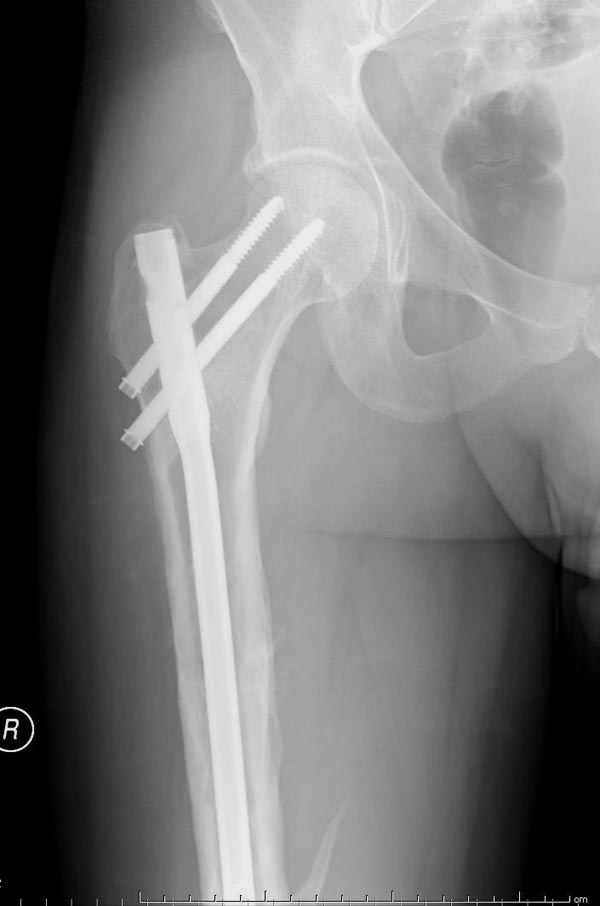

Рутинный интрамедуллярный остеосинтез с расверливанием и с фиксацией реконструктивным трокантерик штифтом (рис №1, №2),

если первые 4 месяца послеоперационного периода проходил без проблем, но на 5 месяце появились боли в дистальном отделе бедра и температура, т.е. симптомы медуллярного инфицирования (рис №3, №4).

Замена реконструктивного штифта “Custom made Nail” с антибиотиком (рис №5, №6),

после промывки канала с рассверливанием внутреннего кортекса, через 4 недели антибиотический штифт удалили, оспалителный процесс остановлен и бедро сросся.